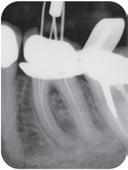

Høykonsentrert kalsiumhydroksid på >41%. pH 12,4 gir høy antibakteriell effekt, bakteriedrepende. Røntgenkontrast. Langvarig. Klar til bruk, appliseres direkte gjennom steril kanyle. Før 489,391,-

Vnr. 3642

Høykonsentrert tyntflytende kalsiumhydroksidpasta med >41% hydroksid i en konsistens som enkelt appliseres med en liten og fleksibel plastkanyle: Flexi-Tip. Autoklavérbare Flexi-Tip i kombinasjon med den myke konsistensen sparer deg for tid, og hjelper deg å oppnå en presis og dyp applisering. pH 12,4 gjør den baktericid. Langvarig. Røntgenkontrast.

858,-

Vnr. 3646

Calasept Plus Flexi-Tip, 100-pk

Directa #1241100

Sett med Calasept Plus 4 x 1,5ml, m/20 Flexi-Tip kanyler: Directa #1240100

589,-

Vnr. 3645

Sterile skyllekanyler med rund spiss og åpning på begge sider slik at væsken virvles rundt. Kan bøyes. Luer-lock.

31G, lilla, 25-pk #1201610

Skyllevæske til kjemisk utvidelse av rotkanaler. Letter den mekaniske utrenskningen. Leveres med adapter til skyllesprøyten. Nå 250ml.

789,-

Vnr. 3647

Flaske 250ml

Directa #1260100

Vnr. 3641

27G, grå, 25-pk #1201600

2% Klorhexidindiglukonat. Benyttes etter EDTA ved revisjonsbehandlinger og alle typer nekrosebehandlinger. Nå 250ml.

Vnr. 3648

Vnr. 3640

Directa #1270100